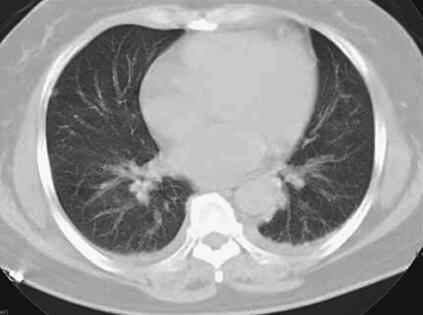

患者,女性,59岁。因“发热8天,上腹部隐痛、腹泻伴胸闷7天”于2011年7月8日入院。患者8天前出现发热,39.5℃,无畏寒、寒战,在当地卫生院予输液治疗(具体不详),症状未好转。7天前出现上腹部隐痛、腹泻,日约4~5次,黄色稀便,伴胸闷,遂就诊于当地镇医院,心电图检查正常,拟“中暑”,予针灸等治疗后无好转。2天前就诊于当地县人民医院,查血常规:WBC 8.4×109/L,N 89.2%,Hb 102g/L,PLT 92×109/L;肥达反应阴性;肝功能:ALT 104IU/L,AST 144IU/L,TP 55g/L,ALB 27g/L;腹部CT:脂肪肝,脾肿大;胸部CT:两肺少许炎症,左侧可疑少许胸腔积液,拟败血症,中毒性肝炎,伤寒住院治疗;期间体温波动于38~39℃,血压波动于80/50~90/60mmHg,予多巴胺[6.0μg/(kg·min)]升压,予亚胺培南-西司他汀钠联合头孢曲松抗感染治疗,病情无好转,仍有发热、腹泻、上腹部隐痛不适,并出现尿量减少、血肌酐升高。于7月8日转笔者医院急诊,测血压[多巴胺6.0μg/(kg·min)维持]89/55mmHg,血常规:WBC 10.28×109/L,N 89.4%;Lac 2.3mmol/L,CRP>90.0mg/L,Cr 141μmol/L,cTnI 6.02μg/L,BNP 577pg/ml;胸腹部CT:两下肺背侧散在炎症,两侧胸腔少量积液,慢肝样病变,胆囊结石(图1、图2);腹部B超:脂肪肝,脾偏大,拟发热待查,心肌炎?感染性休克?,予补液、亚胺培南-西司他汀钠控制感染,多巴胺升血压,为进一步治疗拟上述诊断收入急诊重症监护病房。既往史:40年前发现胆囊结石。

图1 胸腹部CT:两肺纹理增多增粗,两下肺背侧见斑片高密度影,边界模糊;两侧少量胸腔积液(7月8日)

关于恙虫病的肺部改变报道较多。有59%~72%的恙虫病患者可有肺部表现,胸部CT表现可以有磨玻璃影、纵隔淋巴结肿大、小叶间隔增厚、胸腔积液、肺门淋巴结肿大,间质增厚、实变,小叶中心性结节。恙虫病可伴有急性呼吸窘迫综合征(ARDS),是一种少见但很严重的并发症。年龄大、血小板减少、早期肺炎(出现呼吸窘迫前2天,胸片上出现浸润征象)均是ARDS的诱发因素。该患者表现为呼吸促,胸部CT表现为双肺纹理增多、增粗,两下肺背侧见斑片样高密度影,边界模糊;两侧少量胸腔积液,氧合指数<200,考虑并发ARDS。